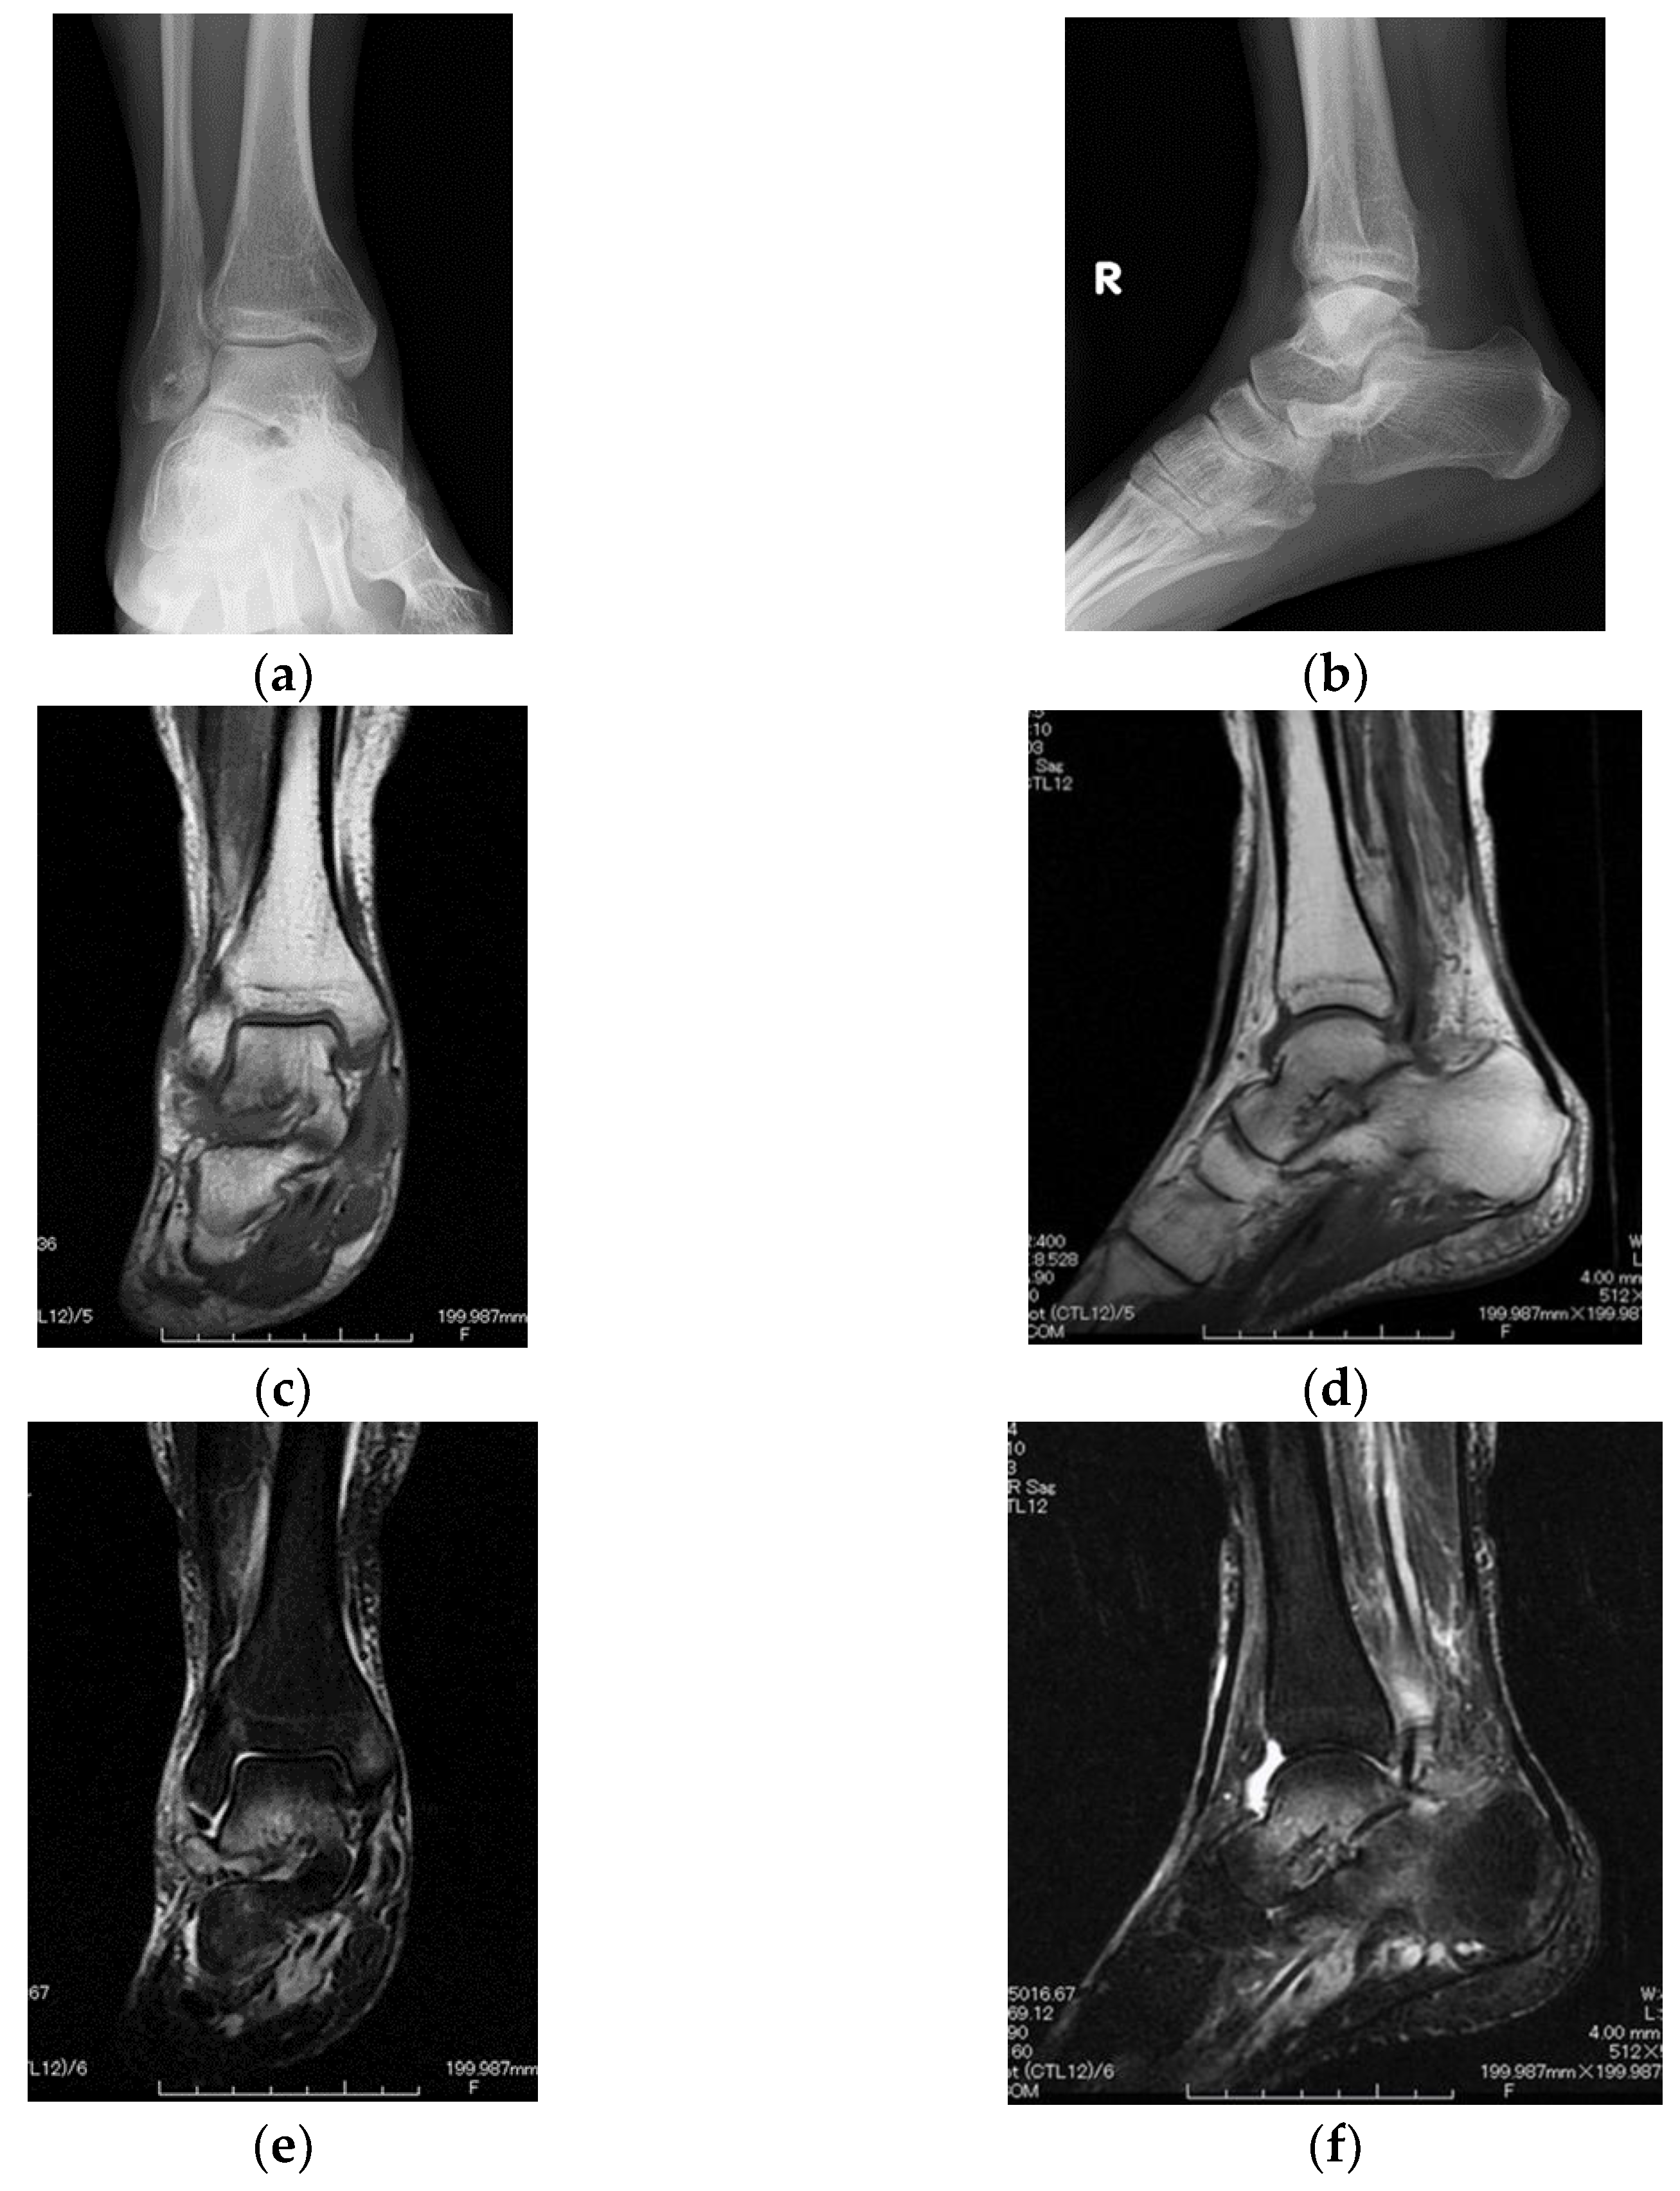

2. Case Presentation